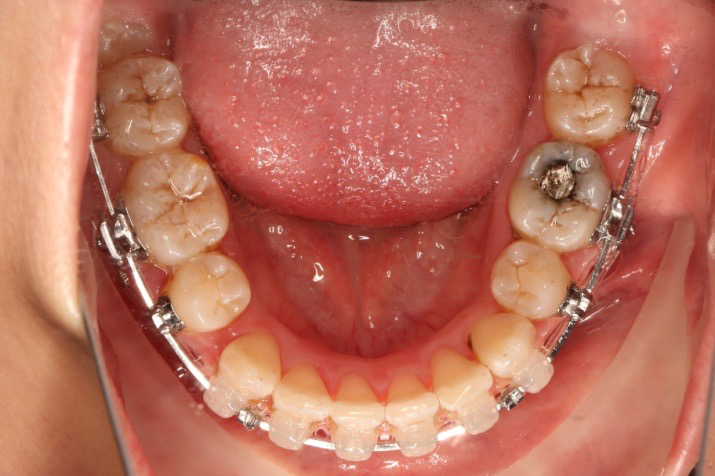

IntraoralExamination(2016-08.31,Wu)

• 磨牙,尖牙I类关系,中线齐

• 上下牙列中度拥挤

• 上下前牙唇倾

2018.11.14  术后磨牙尖牙I类关系,中线齐,覆合,覆盖正常